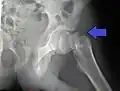

So genannte nichtdislozierte (also unverschobene) bzw. eingestauchte mediale Schenkelhalsfrakturen mit flachem Frakturneigungswinkel werden häufig mittels so genannter Zugschrauben behandelt (siehe Abbildung). Es handelt sich um hohle Schrauben, die über zuvor eingebrachte Führungsdrähte geschraubt werden (Lochschrauben). Bei jüngeren Patienten versucht man in der Regel, den Oberschenkelkopf zu erhalten. Auch hierzu werden Schrauben verwendet.[12]

- Zugschraubenosteosynthese bei einer medialen Fraktur. Behandlung einer nicht dislozierten medialen Schenkelhalsfraktur bei einer 92-jährigen Patientin.

-

Aufnahme vor der OP. a.p.-Aufnahme. Die Fraktur ist mit einem Pfeil markiert. -

Seitliche Aufnahme. Die Fraktur ist mit einem Pfeil markiert. -

Nach OP mit Zugschrauben, a.p.-Aufnahme. Man sieht die noch liegende Redondrainage. -

Seitliche Aufnahme.